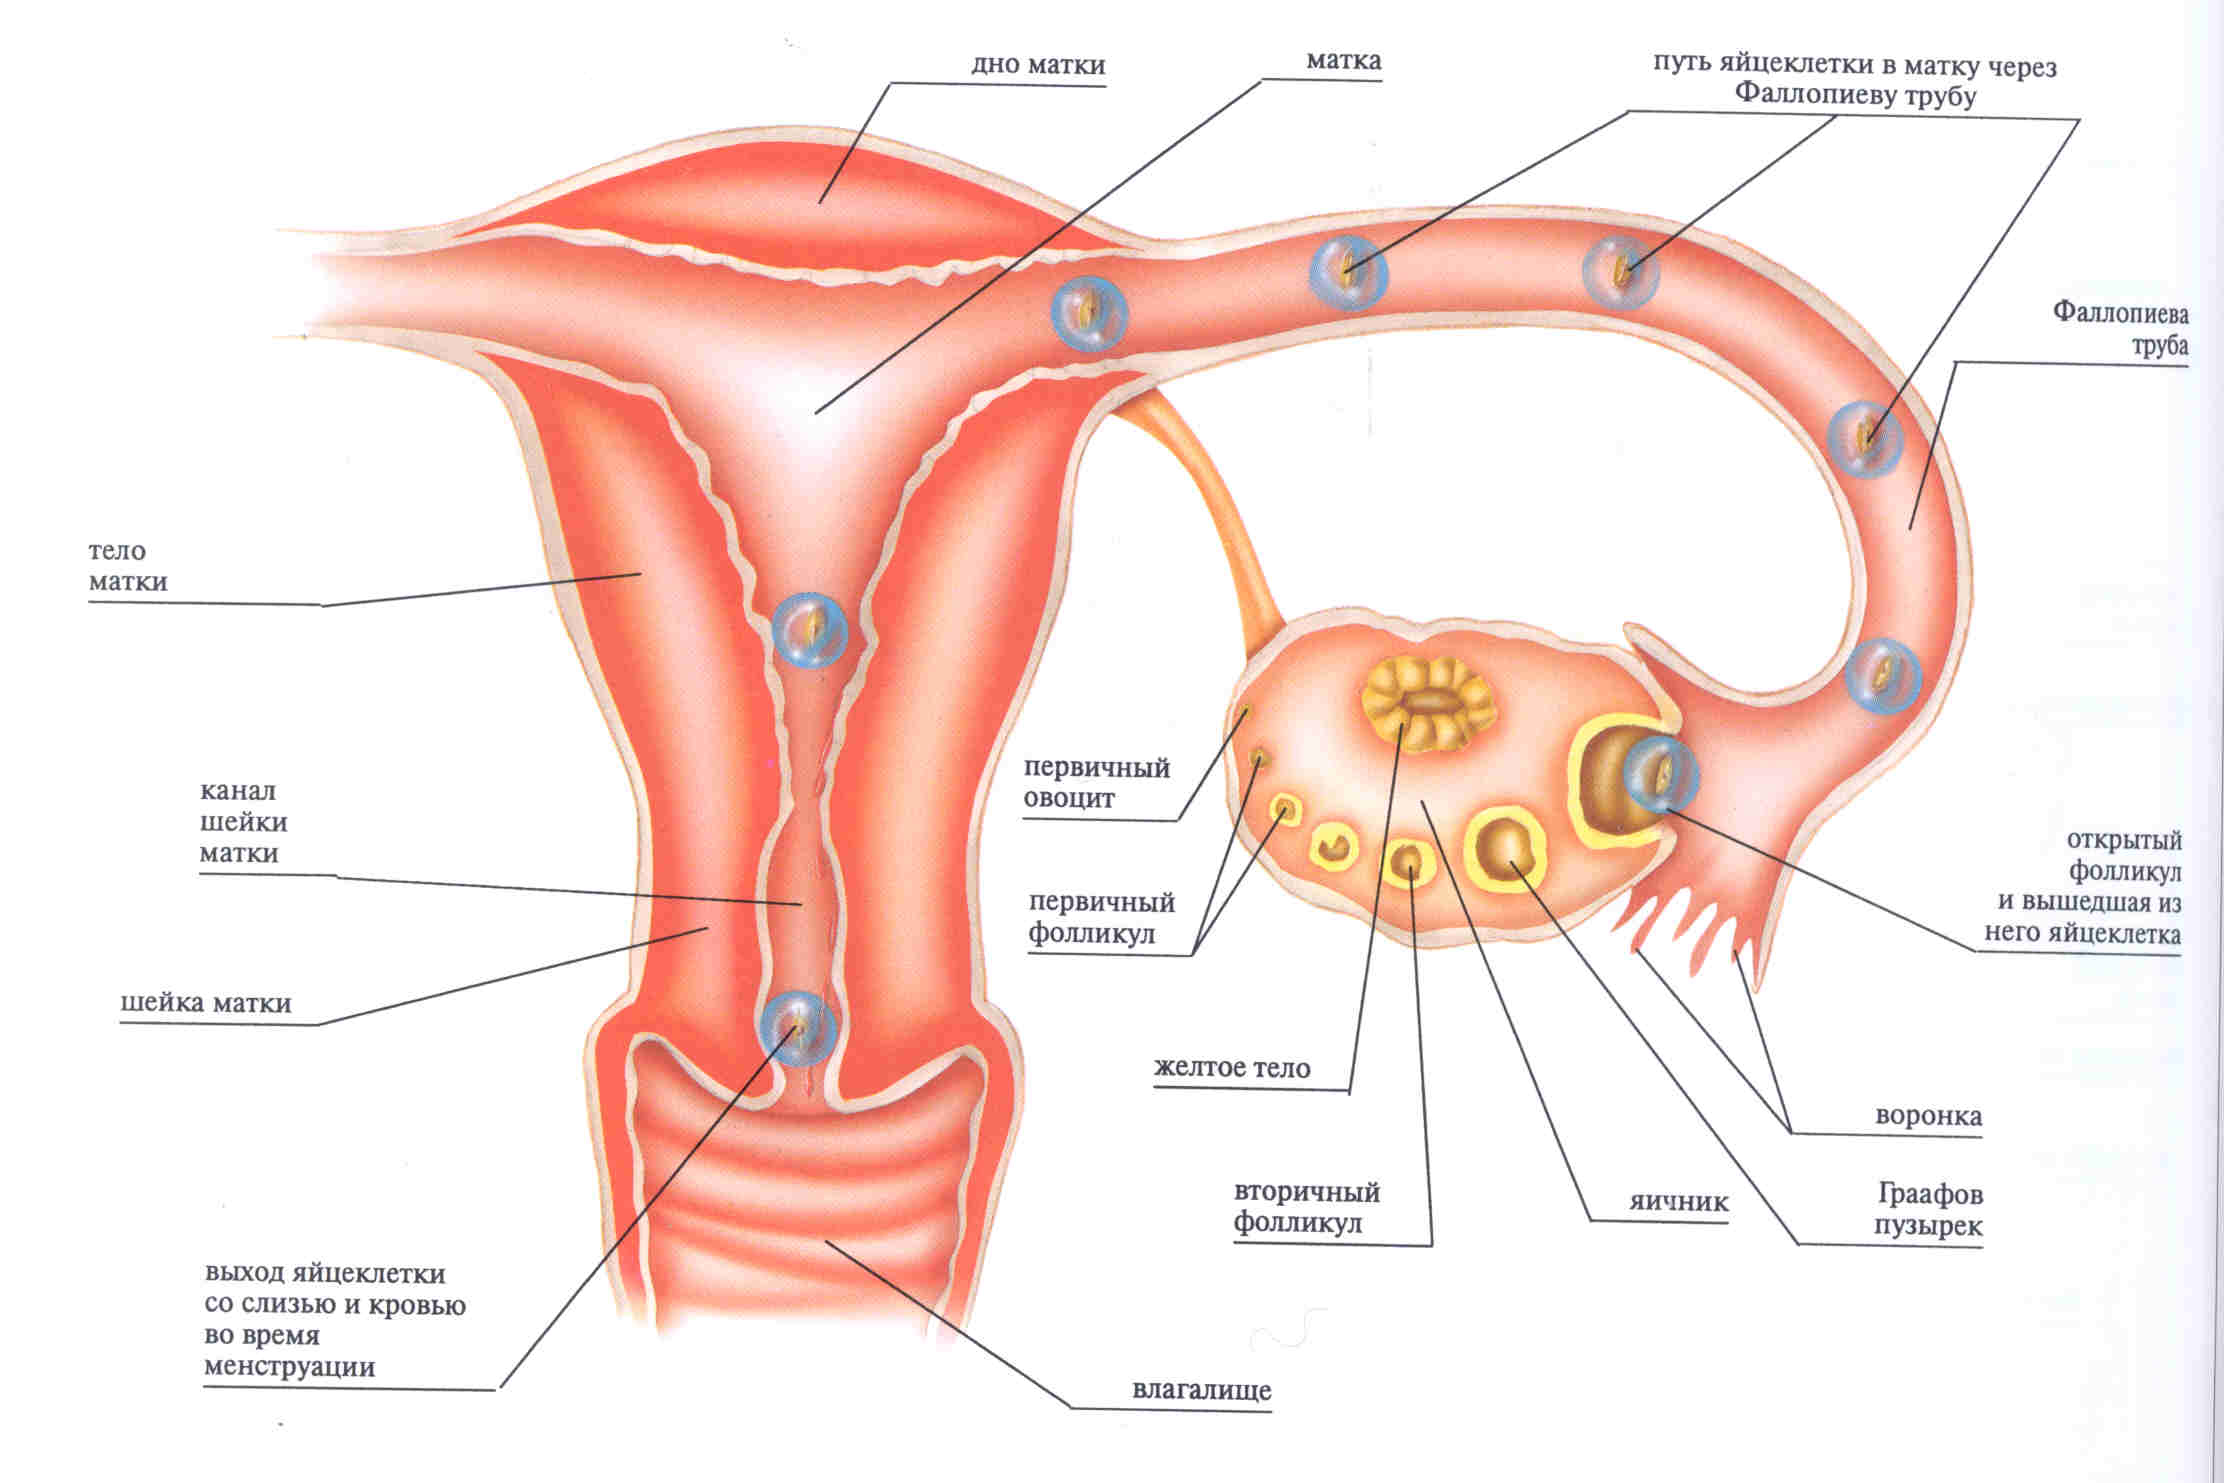

Анатомия женского организма: строение и функции матки

Раздел: Фотопуть к знанию